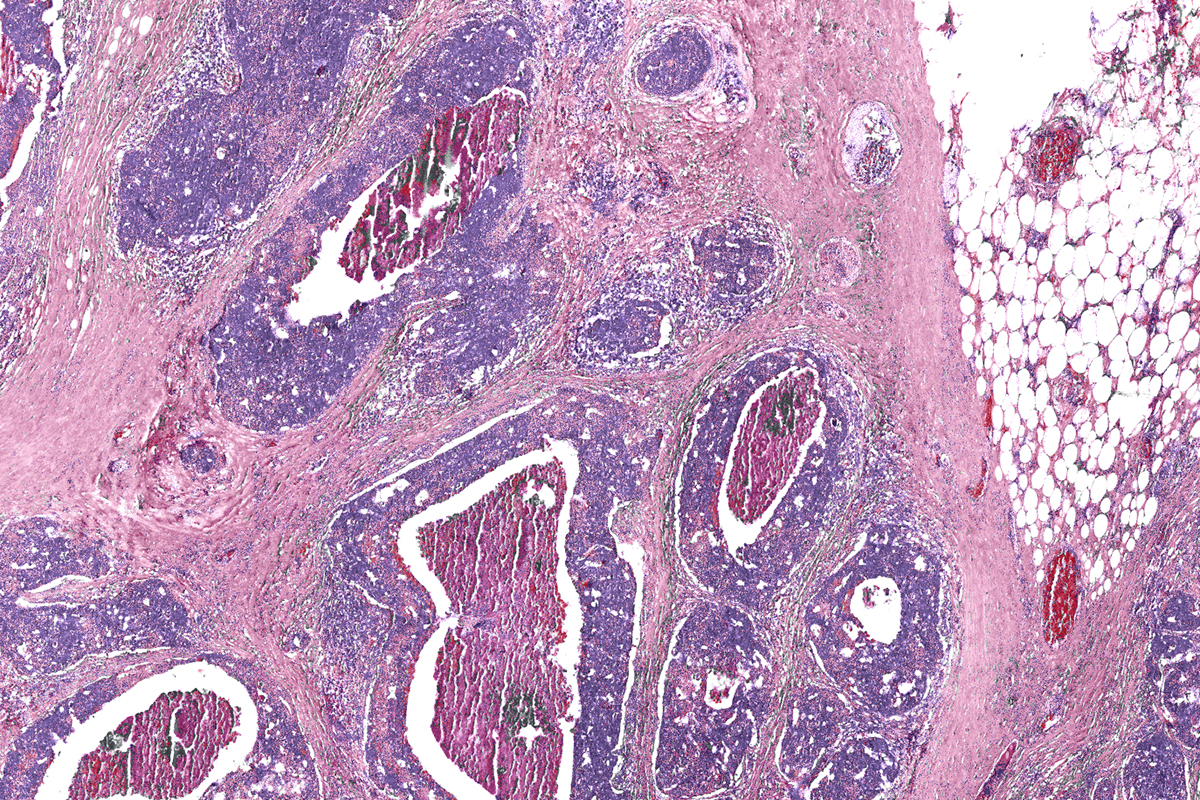

Machine-learning tools can analyze the data from the infrared-optical hybrid microscope to create digital versions of standard dyes, left, or to identify tissue types based on their chemical composition, right.

The researchers verified their microscope by imaging breast tissue samples, both healthy and cancerous, and comparing the results of the hybrid microscope’s computed “dyes” with those from the traditional staining technique. The digital biopsy closely correlated with the traditional one.